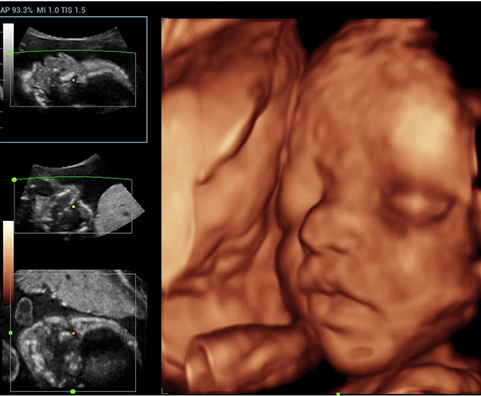

AdemÃĄs de una calidad superior de la imagen, el Resona 7 tambiÃĐn mejora las capacidades de investigaciÃģn clÃnica gracias al revolucionario V Flow para la evaluaciÃģn hemodinÃĄmica vascular y la adquisiciÃģn de planos mÃĄs inteligente a partir de un conjunto de datos 3D para el diagnÃģstico CNS fetal. Combinando el funcionamiento multitÃĄctil mÃĄs intuitivo basado en gestos y todas las funciones clÃnicas esenciales, el Resona 7 estÃĄ realmente encabezando nuevas ondas en la innovaciÃģn del campo del ultrasonido.